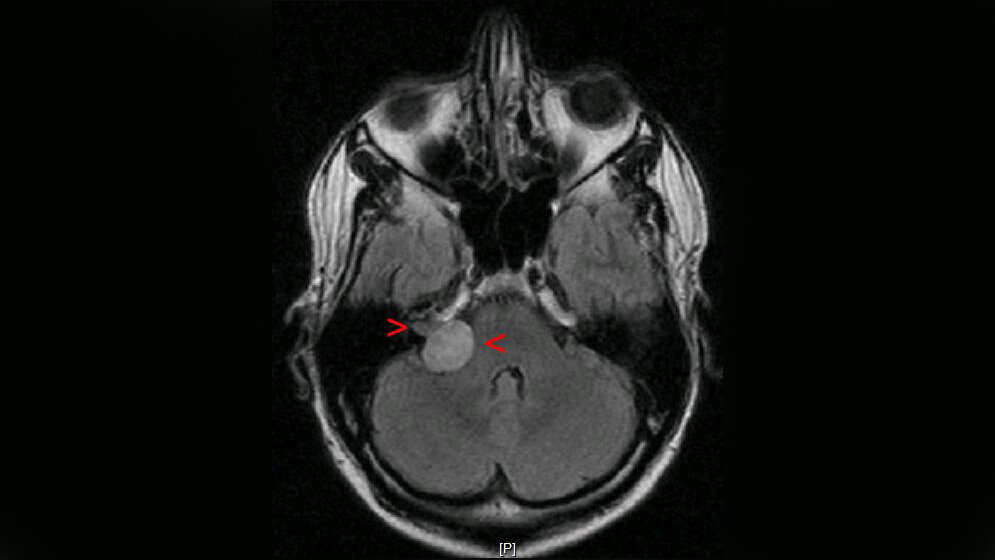

Akustikusneurinome sind gutartige Tumore, die im inneren Gehörgang oder im Kleinhirnbrückenwinkel wachsen und zumeist mit einer einseitigen Hörminderung, einem Tinnitus und Schwindel auffallen. Sie können prinzipiell beobachtet, bestrahlt oder operiert werden. Ab einer gewissen Tumorgröße ist allerdings immer eine Operation erforderlich, wobei danach häufig eine weitere Verschlechterung des Hörvermögens bis zur Ertaubung auftritt. In einer von der halleschen Universitätsmedizin geleiteten klinischen Phase-III-Studie an neun deutschen Klinika soll nun herausgefunden werden, ob die Gabe der Substanz Nimodipin einige Zeit vor und nach der Operation eines Akustikusneurinoms eine neuroprotektive Wirkung hat und die Hörfunktion häufiger erhalten werden kann. Die Deutsche Forschungsgemeinschaft (DFG) fördert die Studie mit insgesamt rund 900.000 Euro für drei Jahre.

Das Akustikusneurinom macht etwa sechs bis acht Prozent der intrakraniellen Tumoren aus und kann unbehandelt auch zum Tode führen. Statistisch erkranken jährlich etwa ein bis zwei Menschen je 100.000 daran. „Diese Tumoren sind jedoch sehr gut behandelbar. Nach kompletter operativer Entfernung sind die Patienten, die im Durchschnitt zwischen 45 und 55 Jahre alt sind, in der Regel geheilt. Allerdings geht mit dem einseitigen Verlust der Hörfunktion eine massive Beeinträchtigung der Lebensqualität einher“, sagt apl. Prof. Dr. Christian Scheller von der Universitätsklinik und Poliklinik für Neurochirurgie des Universitätsklinikums Halle (Saale), der seit über 20 Jahren zu der Thematik forscht, wissenschaftlich publiziert und diese Tumoren operiert. Zur Einordnung: Die Universitätsklinik für Neurochirurgie ist auf die operative Behandlung von Akustikusneurinomen spezialisiert und dafür kommen aus ganz Deutschland Patienten nach Halle. Außerdem wird hier an dem Thema seit mehr als 20 Jahren wissenschaftlich gearbeitet. Das habe sicher dazu beigetragen, dass die DFG dieses Vorhaben fördere, so Scheller.